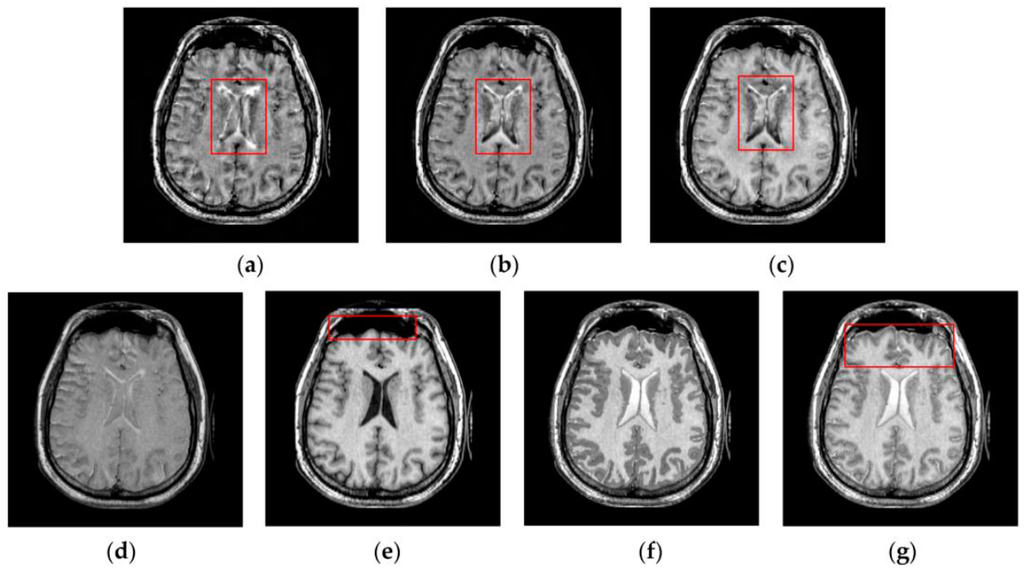

4.2. Visual Comparisons of Fused Results